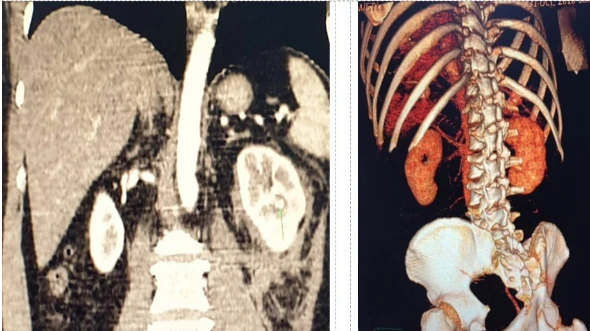

Kết quả chụp CT scanner cho thấy ông Q. có một vết thương xuyên từ vùng lưng làm rách 1/3 giữa thận trái xuyên vào bể thận.

Kết quả chụp CT scanner cho thấy ông Q. bị vết thương thận trái. Ảnh: BVCC